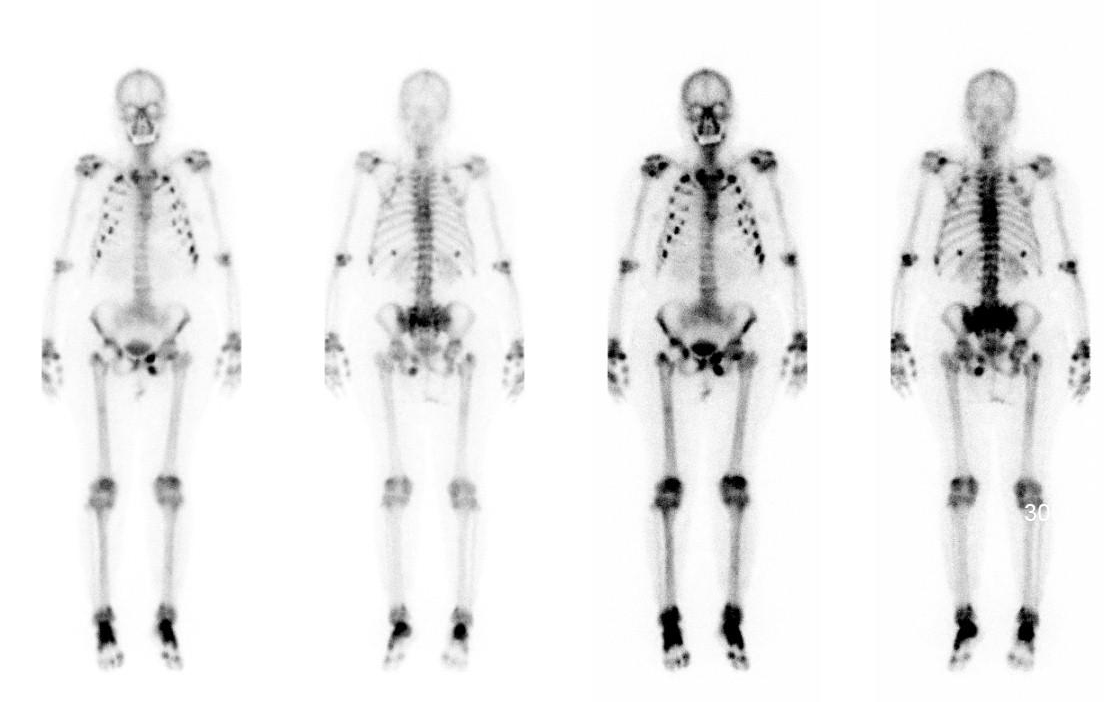

辅助检查:我院全身ECT骨显像+断层:双侧多根肋骨、第7、8、10、11、12胸椎、第1腰椎、左侧耻骨支、坐骨支、耻骨联合、双侧肩关节、肘关节、腕关节、骶髂关节、髋关节、踝关节可见多处放射性浓聚CT定位相可见多处肋骨、肋软骨连接处假骨折。胸腰椎正侧位片示:胸腰段骨质密度减低,骨皮质变薄或皮质线不连续,腰3-5椎体术后改变。骨盆前后位片示:左侧耻骨上下肢骨折,左股骨干上缘外侧皮质刀割样假骨折,右髋关节置换术后改变,腰椎内固定术后改变,右侧耻骨下支骨折。双髋关节CT示:左侧耻骨上下支骨折畸形愈合,右侧耻骨下支骨折,骶骨、左侧股骨颈陈旧骨折改变,右髋关节置换术后改变。曾行全身PET未发现肿瘤。

▼ 本院全身骨显像+断层: